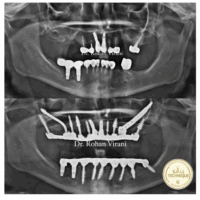

Case Study 2 (Female)

case study female 1

case study female 2